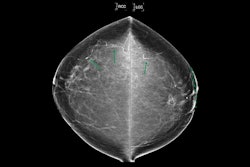

South Korean AI software developer Lunit has achieved the milestone of helping to screen more than 1 million annual mammograms in North America, a year after its purchase of Volpara Health Technologies.

In June of this year, the company expects to have deployed its Lunit Insight DBT and Lumit Insight MMG in more than 200 imaging centers and hospitals across the U.S., with 350 to 400 radiologists using the technology.

Lunit's customer base includes Rezolut, SimonMed Imaging, and the University of California Davis Health, it said. It was founded in 2013.